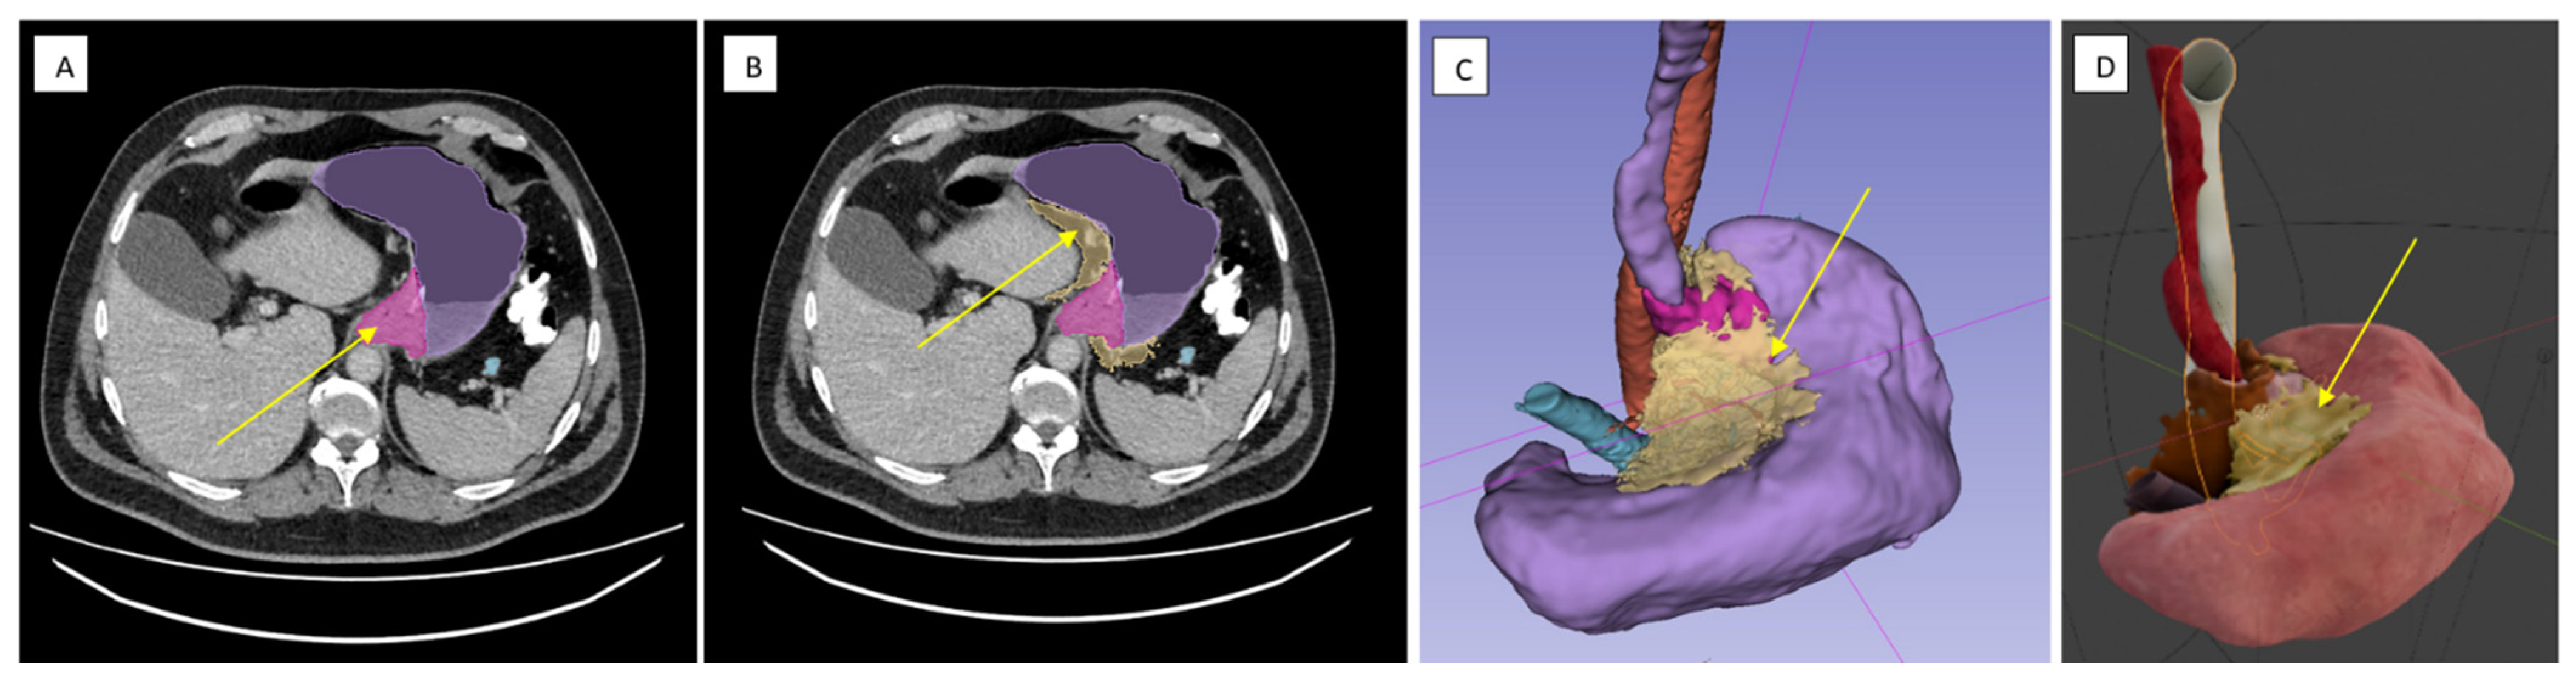

2.3. Technical Aspects of the Surgical Procedures

2.3.1. Surgical Dissection Planes and Landmarks: Critical Steps of Gastrectomy in the Embryonic Plane